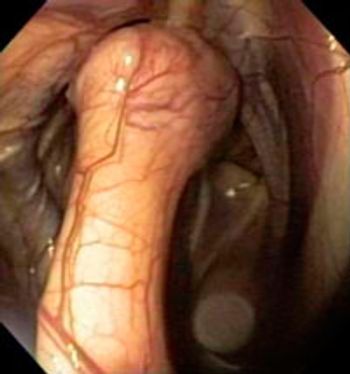

The three most common gastrointestinal problems that are seen in the foal include colic, gastric ulcer disease and diarrhea. Though these are also common in the adult the foal has different specific etiologies and treatments.

Older horses can present with the same problems as the younger horse but there are a few specific problems that occur with age or worsen with age.